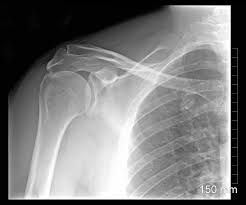

Think of the epiphyseal line as a permanent mark that tells us the bone has finished growing. You can see this line on an X-ray, and it’s helpful for doctors to determine bone age, which is particularly important for evaluating growth and development in children and adolescents.

For example, if a doctor sees that a child’s epiphyseal lines are still open, it means that the child is still growing. Conversely, if the epiphyseal lines are closed, it means that the child has reached their full height. This is also useful for understanding the healing process after a bone fracture. The presence of an epiphyseal line can help determine the location of the fracture and the extent of bone growth that has occurred since the injury.

Here’s the thing: we can’t actually see the growth plates directly. They’re inside the bone. But, we can use X-rays to see the epiphyseal line, which is like a ghost of the growth plate once it’s closed.

The epiphyseal line will show up as a thin, dense line on the X-ray. It’s not super obvious, but an experienced doctor or radiologist can spot it.

Growth and Development: The presence of the epiphyseal line means bone growth is finished. It’s a helpful way to track a child’s development and make sure everything is on track.

Injury and Repair: Sometimes, injuries can affect the growth plates. For example, a fracture that crosses a growth plate could cause growth problems. The epiphyseal line helps doctors understand if the injury is affecting growth.

Medical Conditions: Certain medical conditions can cause premature closure of the growth plates. This can lead to stunted growth. The epiphyseal line is helpful for identifying these conditions.